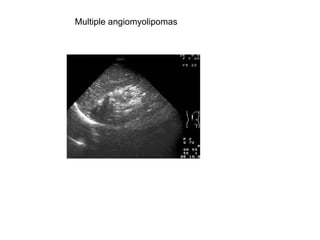

Multiple angiomyolipomas